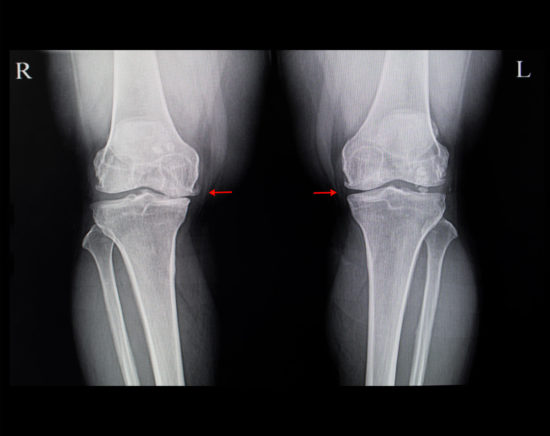

Osteoarthritis (OA) is the most common joint disease and one of the most prevalent symptomatic health problems. Knee osteoarthritis (KOA) leads to knee pain and altered joint function, with socioeconomic consequences. It generates a high proportion of health costs in many countries and has become a major public health issue. The health costs are directly related to KOA, such as knee replacement, or substantially by medication consumption.

In the many studies investigating the risk factors of KOA, overweight and obesity remain the most determinant even though they are considered modifiable. A recent meta-analysis showed a 5-unit increase in body mass index (BMI) associated with a 35% increased risk of KOA (relative risk [RR]: 1.35; 95% confidence interval [CI]: 1.21–1.51). BMI was positively associated with increased risk of KOA defined by plain radiography and/or clinical symptoms (RR: 1.25, 95% CI: 1.17–1.35) and clinical surgery (RR: 1.54, 95% CI: 1.29–1.83). Another study suggested a longitudinal association between weight gain and increased risk of symptomatic OA. The Framingham study showed an association of decreased BMI by ≥2 units at 10 years before examination and 50% decreased risk of OA for women. In another cohort study, a weight loss of >10% could reduce the clinical consequences of OA, finding a dose–response association between weight loss and pain or articular function.

Despite obesity being a risk factor for KOA, we have few data on the association of obesity severity and its clinical and functional consequences. This study aimed to describe the association between KOA and BMI gradation in terms of pain, physical disability, level of PA, and fears and beliefs concerning KOA.